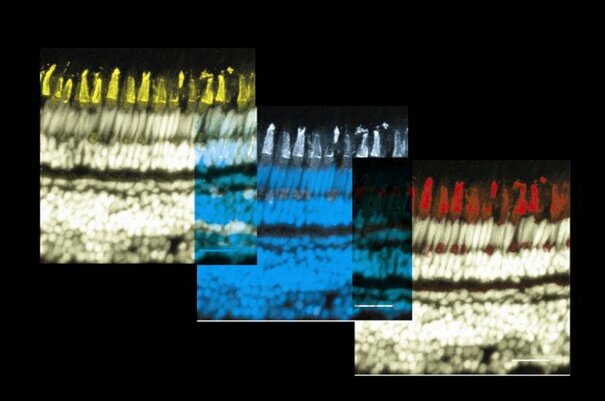

Source: Clean water is equally important for everyone. Contaminated water can lead to sudden mass mortalities of animals such as these cockles. My research involves developing a universally applicable microarray to detect waterborne pathogens and help ensure our waters are clean." title=""> Source: This is an image through the eye of a zebrafish, showing the neurons in the retina which enable us to see colour." title="">

Source: This is an image through the eye of a zebrafish, showing the neurons in the retina which enable us to see colour." title="">